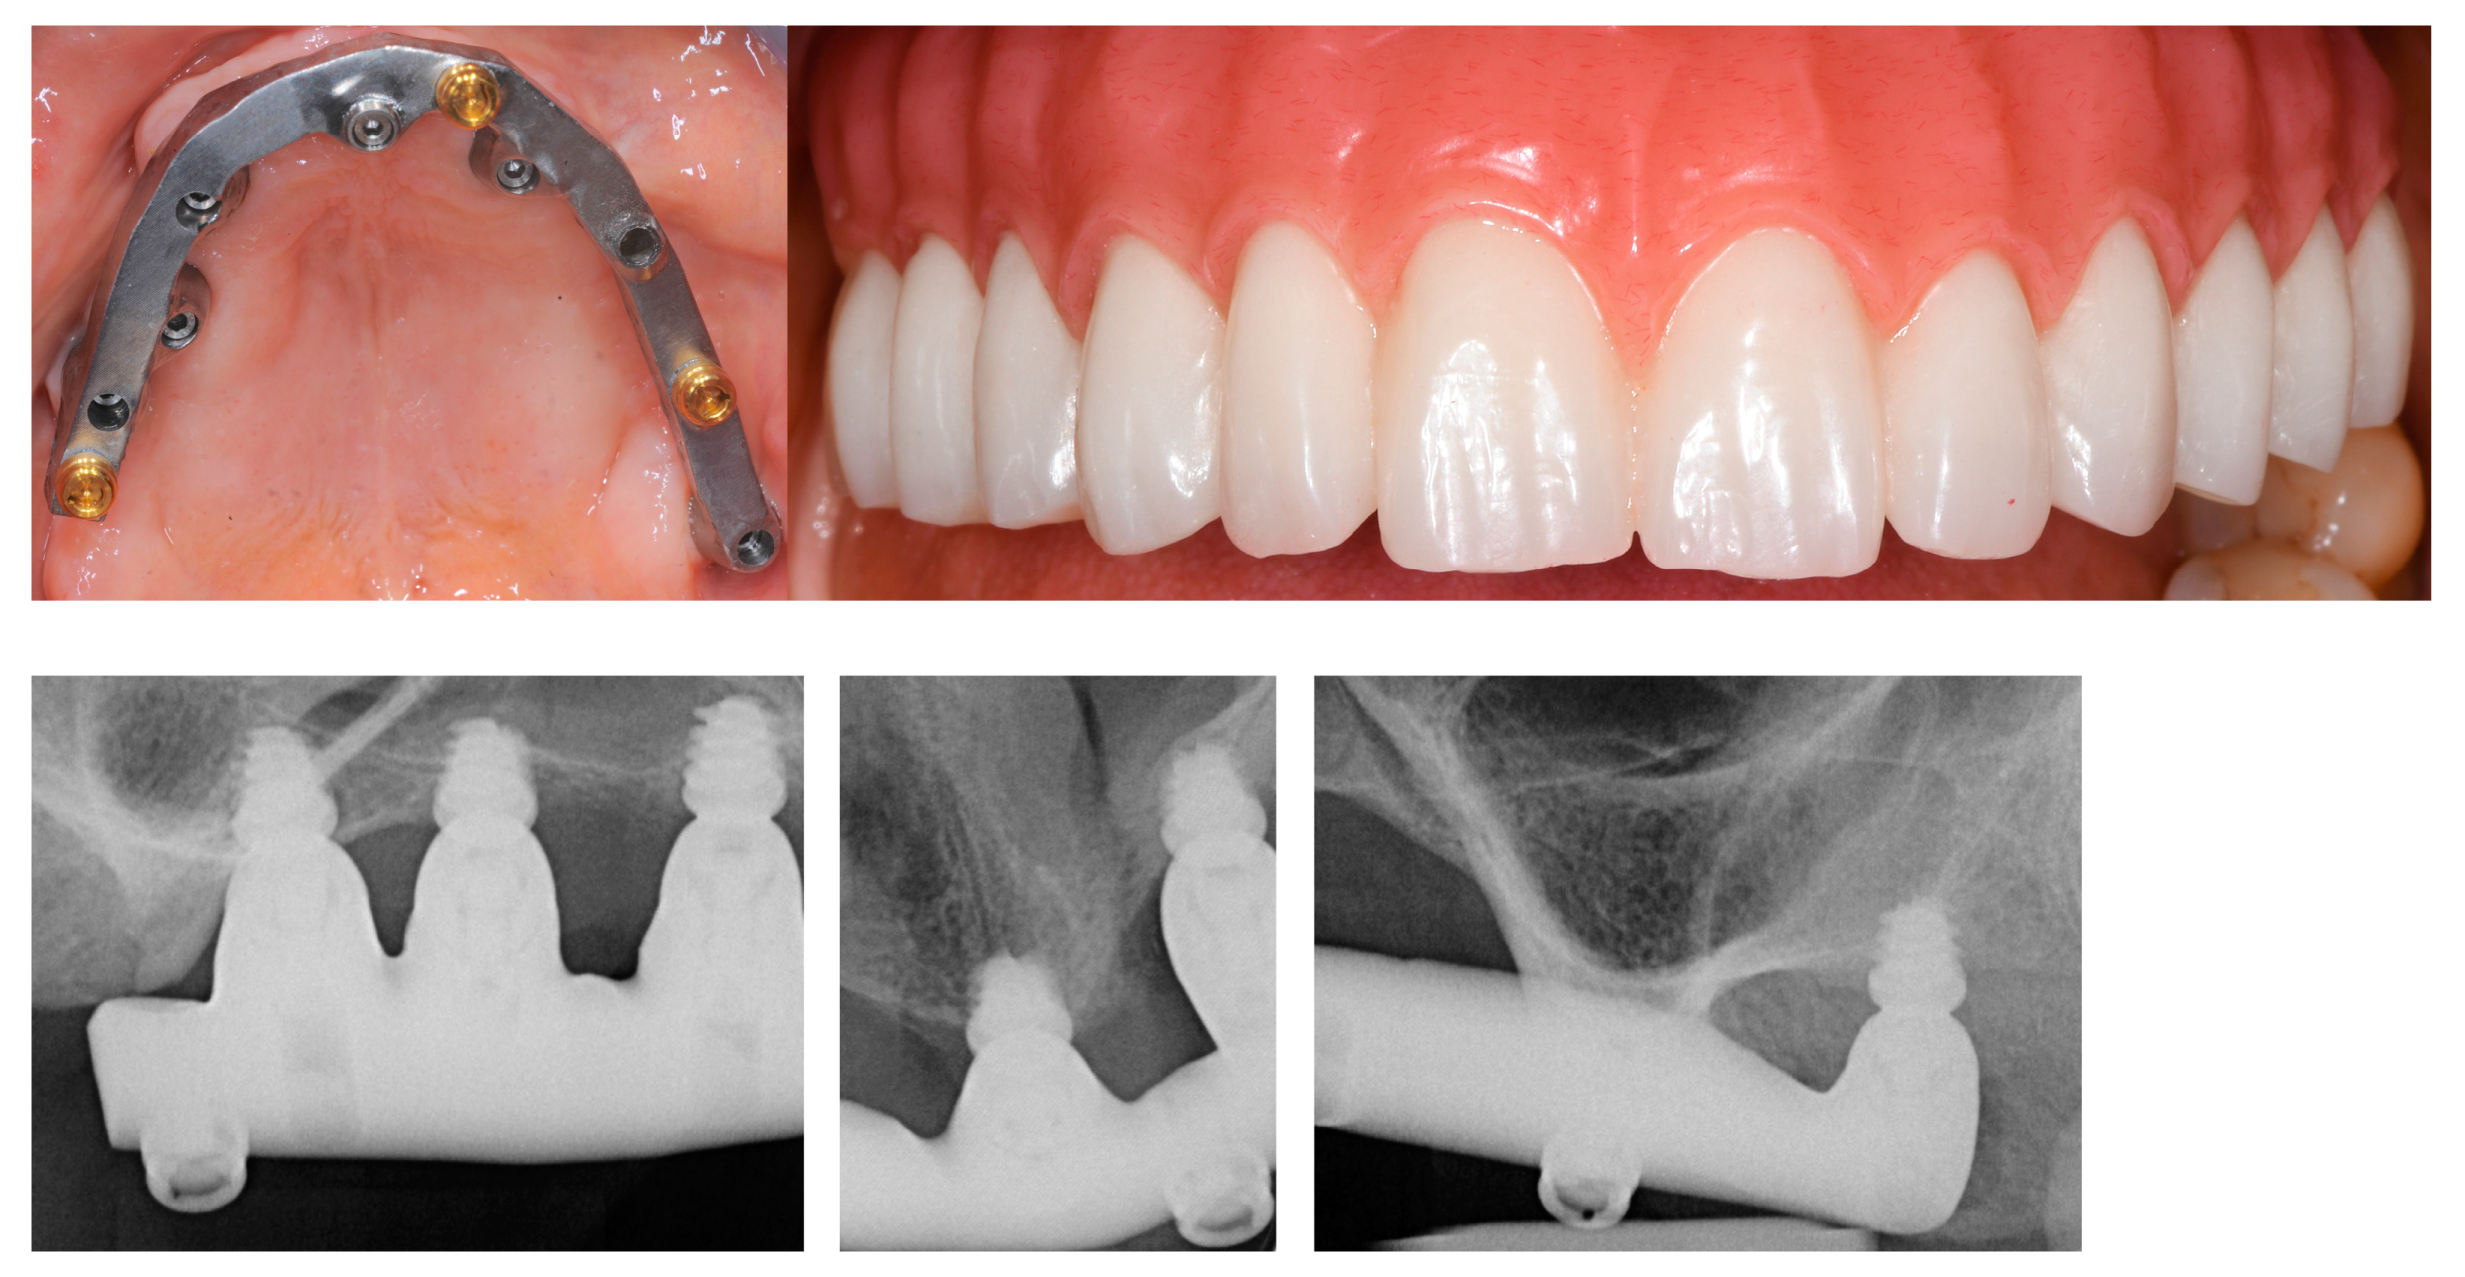

3.4. Overdentures (OVD)